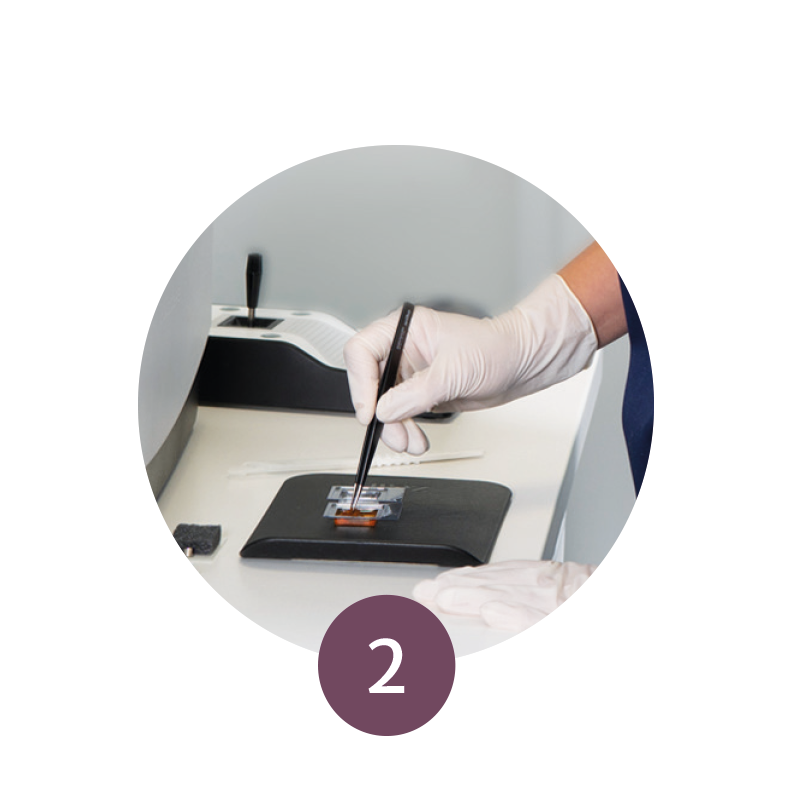

Step 2: Staining Procedure

The specimen is then quickly and easily stained with a fluorescent dye and mounted on a glass slide.

Step 3: Tissue Mounting

The glass slide is subsequently inserted into the VivaScope 2500.